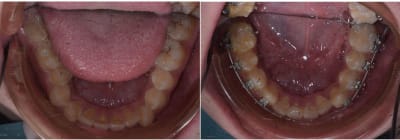

Un cas que je viens de finir.

Je suppose qu'en France l'option chirurgie maxillo facial aurait était proposé, mais au Cambodge c'est réservé pour les cas " lourd "

La patiente a des couronnes soudées de 7 à 5 sur les quatres secteurs.

J'ai utilisé des minivisse à la Chilles dans les secteur post mandibulaire pour renfocrée l'ancrages.

De simple élastique de class III aurait suffit pour obtenir une occlusion correct mais aurait conduit à la proclination des incisives sup ce qui aurait était détrimental pour la ligne du sourires.

L'option miniscrew m'a permit d'utiliser des élastique de class II et d'augmenter la visiblité des incisives.

Un peut moins de deux ans de traitement.

J'ai utilisée les minivisse de Chilles pour renforcer/distalizer les secteurs mandibulaire.

Les Minvisse te permettent d'utiliser des élastique de class II pour obtenir une retroclination des incisives supérieur.

Pour les cas de bi protrusion avéolaire c'est le même principe. Minivisse à la mandibule et class II pour distaliser l'arcade supérieur

Traitement par bagues metal en vestibulaire.

Pour la contention si tu regarde les super imposition tu verras que seul les incisive inf on subit un déplacement important, vue que le bite est bon je ne me fait pas trop de soucie pour la stabilité.

Pour l'instant la patient à de simple gouttiére en plastique, je l'ai revue aujourd'hui ( une semaine après la dépose des bagues et tout est stable. Je la revois dans deux semaine, un mois , deux mois, trois mois. Puis si tout reste stable, contention collée haut et bas.

Non en faite ce qui c'est passé c'est que j'ai obtenue une configuration plus ouverte des bases osseuse. Sur les patients de class III l'on veut souvent être plus hyperdivergent.

Dans la catégorie cas chirurgical, traité non chirurgicalement celui là est pas mal.

Vue que la patient refusé catégoriquement toute chirurgie, on visait plus une amélioration qu'un résultat parfait.

Le but étant d'amélioré l'occlusion postérieur et l'esthétique. Le set up me disait qu'une occlusion correcte pouvait être possible, mais sur ce type de cas le pouvoir prédictif du set up est limitée.

Aucune minivisse juste extraction de 37 47 et un patient qui est un champion pour porter les élastiques ( commencé dès le début du traitement. )

On en ai à 8 mois de traitement .